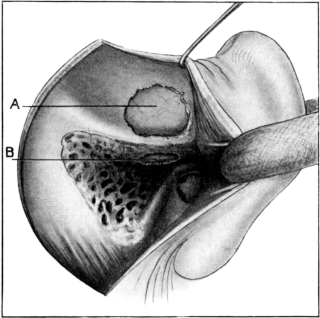

| 135. | Mules’s Operation. First step | 258 |

| 136. | Mules’s Operation. | 258 |